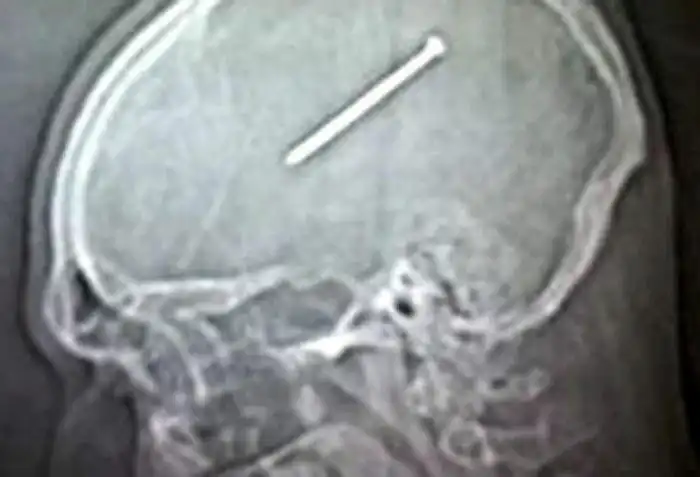

Необычные предметы в теле людей на рентгеновских снимках

На рентгеновских снимках людей порой можно обнаружить самые необычные предметы, которые находятся в их теле.

Человечество явно с гвоздями не дружит!!! Что не снимок то гвоздь в башке!